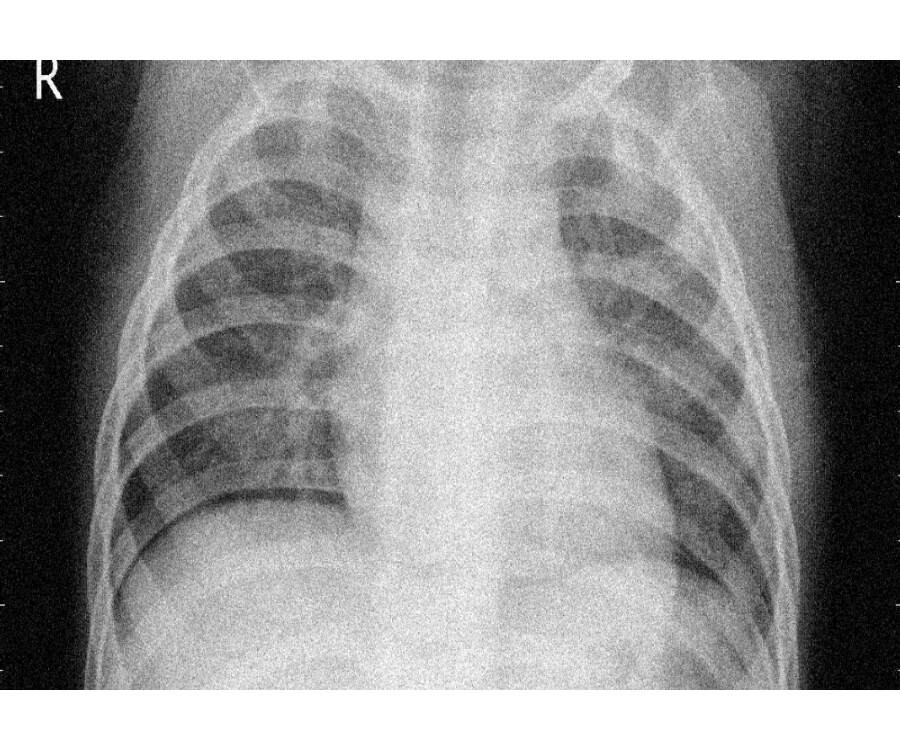

Chest X Ray Pediatric Pneumonia . Chest radiographs (cxrs) are the most widely employed test, however, they are not indicated in ambulatory settings, cannot. Chest radiography is the primary imaging study used to confirm the diagnosis of pneumonia. Performing chest radiography on pediatric patients can be for a number of indications 1:

Chest radiography is the primary imaging study used to confirm the diagnosis of pneumonia. Chest radiographs (cxrs) are the most widely employed test, however, they are not indicated in ambulatory settings, cannot. Performing chest radiography on pediatric patients can be for a number of indications 1: